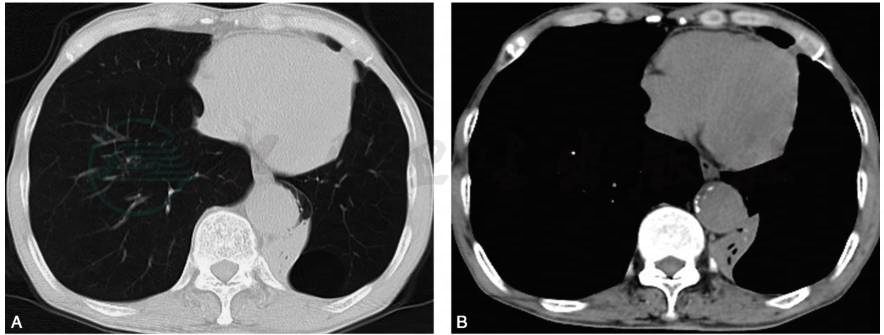

支气管镜下治疗后,患者自觉气促症状明显缓解,仍有咳嗽咳痰。查体:左肺呼吸音较前增强,未闻及干、湿性啰音。1个月后复查肺功能与胸部CT均较前改善(图5,表2),仍残留左下叶背段不张,建议再次气管镜下治疗,患者拒绝。

图5 治疗后1个月复查胸部CT(2017-05-10)

A.左肺上叶较前明显复张,左肺下叶大部肺不张;B.纵隔左偏较前减轻